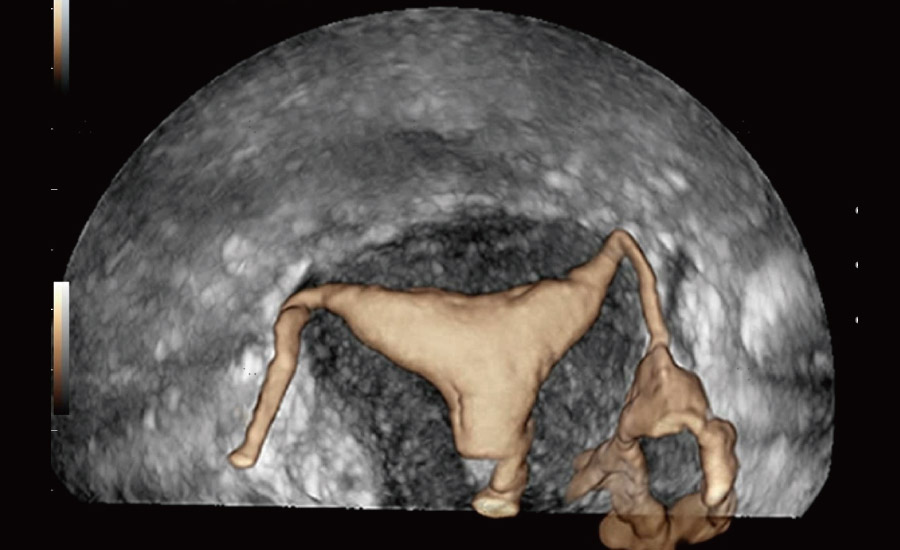

UMA (angiografia ultramicroscĆ³pica)

A tecnologia inovadora elimina as limita??es das tradicionais imagens com Doppler. Com resolu??o espacial e sensibilidade de fluxo ultra-altas, permite a detec??o de perfus?es de fluxos muito sutis e lentos, ampliando assim a aplica??o clĆnica da avalia??o qualitativa e quantitativa do ultrassom no cĆ©rebro fetal, rins, placentas, endomĆ©trios, ovĆ”rios etc.

Por meio da combina??o de algoritmos avan?ados e do conhecimento especĆfico da regi?o, a inovadora solu??o Smart Scene permite a identifica??o automĆ”tica das caracterĆsticas do tecido e fornece diagnĆ³stico especĆfico dos Ć³rg?os com informa??es completas. Com base na identifica??o automĆ”tica de cenĆ”rios, a solu??o realiza n?o apenas a varredura 2D inteligente com configura??es e medidas automĆ”ticas, mas tambĆ©m oferece informa??es 3D abrangentes em todas as etapas, desde a otimiza??o de imagens volumĆ©tricas atĆ© a difĆcil obten??o de planos 2D, e a quantifica??o durante todo o procedimento. Ele ajuda a reduzir em grande parte a dependĆŖncia de habilidades clĆnicas, ao mesmo tempo que aumenta a precis?o, a confian?a e a eficiĆŖncia no diagnĆ³stico.